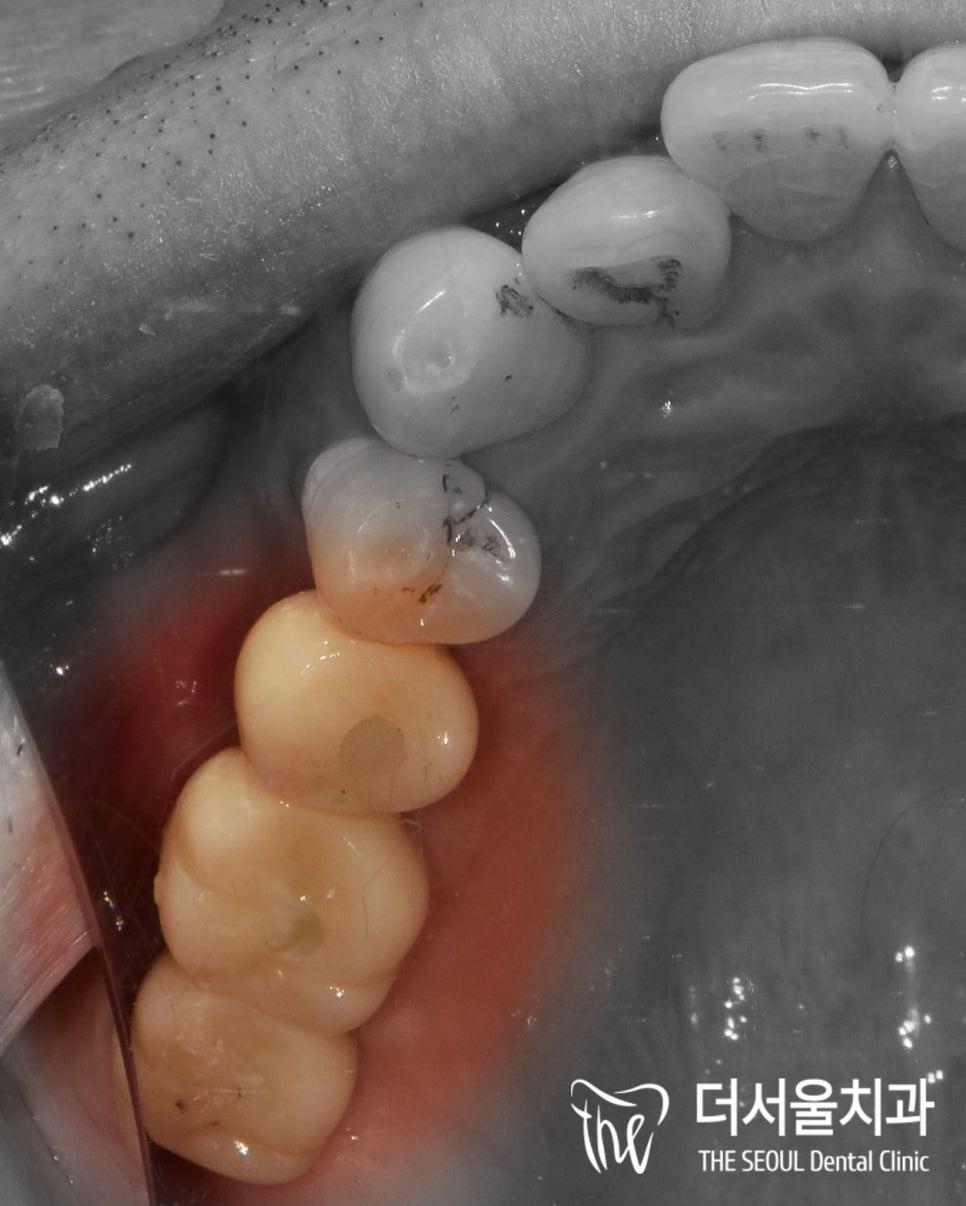

하루에 흡연을 1갑 이상 하시다 보니

전체적으로 착색되거나

상태가 좋지 않은 이들이

몇 개 보이는군요.

잇몸이 많이 안 좋으신 편이라

하루빨리 치료가 필요했기에